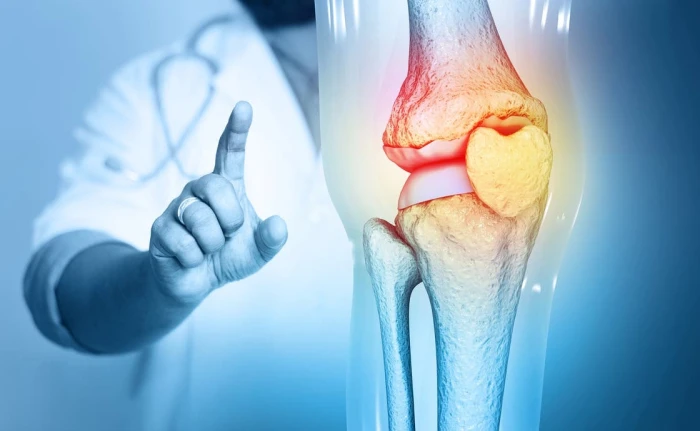

"أكثر من الحليب".. غذاء بسيط يحافظ على صحة العظام بعد سن الخمسين

صحيفة المرصد : كشفت دراسة حديثة نشرها موقع "إيكونوميك تايمز" نقلاً عن مجلة "بريفينشن" أن إدخال بعض الخيارات الغذائية البسيطة إلى النظام اليومي يمكن أن يساعد بشكل كبير في الحفاظ على قوة العظام، خاصة مع تسارع فقدان كثافتها بعد سن الخمسين.

جراحة العظامووفقاً لدانيال ويزنيا، خبير جراحة العظام في كلية الطب بجامعة ييل، فإن جبن القريش يعد من أهم هذه الأطعمة اليومية فعالية لتعزيز صحة العظام، وذلك بفضل تركيبته الغنية بالبروتين والكالسيوم.

الكالسيوموأوضح أن الكالسيوم يوفر المادة الخام اللازمة لتكوين أنسجة العظام، بينما يساعد البروتين في الحفاظ على بنية العظام الموجودة.